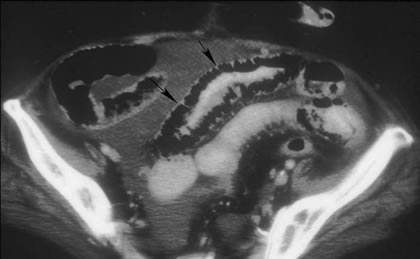

Η αξονική τομογραφία χρησιμοποιείται όλο και περισσότερο στη σύγχρονη διαγνωστική απεικόνιση του ειλεού. Με τη χορήγηση του σκιαγραφικού γαστρογραφίνη, έχει τη δυνατότητα να αναδείξει διατεταμένο εγγύς και συμπεπτοκός περιφερικά του σημείου της απόφραξης λεπτού εντέρου, βοηθώντας στην ταυτοποίηση του «σημείου μετάπτωσης», που αντιστοιχεί στο ύψος της απόφραξης του εντέρου. Με μεγαλύτερη ευαισθησία από την απλή ακτινογραφία, μπορεί να αποκαλύψει την παρουσία αέρα μέσα στο τοίχωμα του εντέρου, ακτινολογικό σημείο χαρακτηριστικό της ισχαιμικής απόφραξης.

Αξονική τομογραφία: παρουσία ενδοτοιχωματικού αέρα λόγω ισχαιμικής απόφραξης